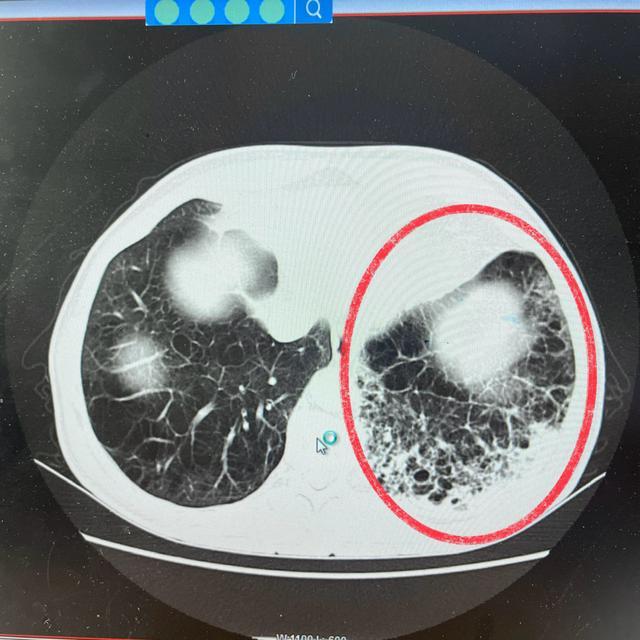

(出院时肺部CT)

经过精心治疗,6月13日的复查结果显示:白细胞计数回落至3.62×10^9/L,C反应蛋白也下降至86.91mg/L,血常规指标已显著改善,喘息与气促症状明显缓解,偶有的咳嗽,畏寒发热症状也已完全消失。患者病情好转,于6月16日办理了出院手续。